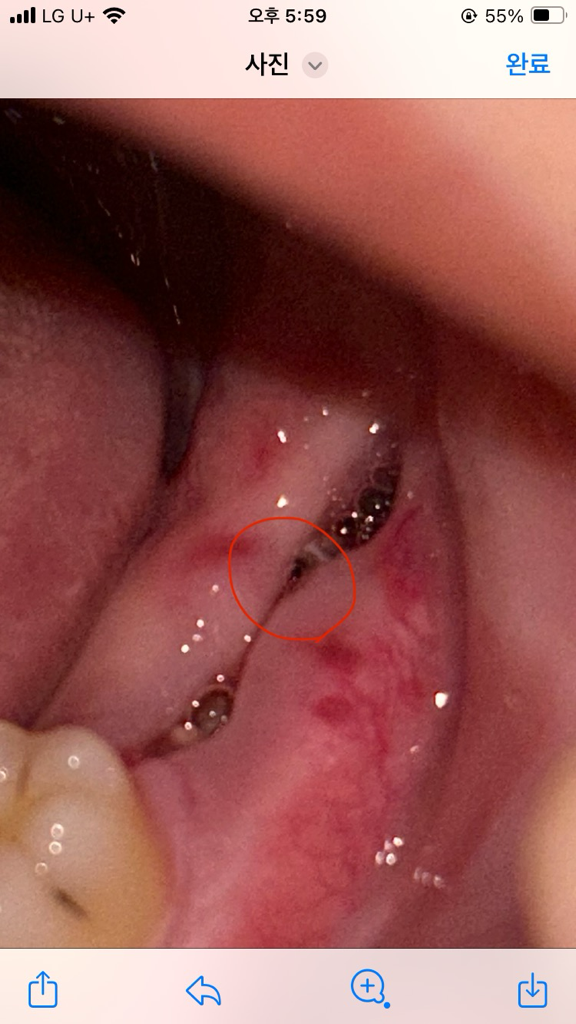

오늘 사랑니 실밥 뽑았는데 실밥 남은건가요?

오늘 사랑니 실밥 뽑았는데 뽑은자리에 까만 선?점?같은게 있는데 이거 실밥 덜뽑은건가요? 아니면 피딱지인가요 뭔지알려주세요

실밥이 아니라 잇몸안쪽이 까맣게 보이는것처럼 보입니다. 크게 신경쓰지 않으셔도 될것같습니다.

사진으로는 실밥인지 아닌지 확실히 알아보지는 못하겠지만 피딱지일 가능성이 높아보입니다.

사진으로 봤을 경우에는 실밥은 다 제거된 것으로 보입니다. 해당 부위는 실밥 등으로 인해서 잇몸에 나이는 상처이기 때문에 대부분 시간이 지나면서 아무는 경우가 많습니다.

현재 해당부위에 혈병이 생긴 것을 보이며, 억지로 떼어내지 말고 자연스럽게 떨어지도록 두길 권합니다.